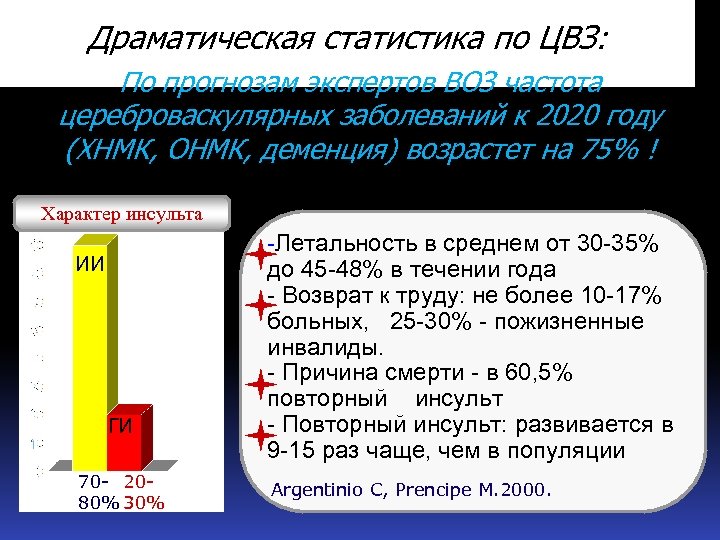

Драматическая статистика по ЦВЗ: По прогнозам экспертов ВОЗ частота цереброваскулярных заболеваний к 2020 году (ХНМК, ОНМК, деменция) возрастет на 75% ! Характер инсульта ИИ ГИ 70 - 2080% 30% -Летальность в среднем от 30 -35% до 45 -48% в течении года - Возврат к труду: не более 10 -17% больных, 25 -30% - пожизненные инвалиды. - Причина смерти - в 60, 5% повторный инсульт - Повторный инсульт: развивается в 9 -15 раз чаще, чем в популяции Argentinio C, Prencipe M. 2000.

Драматическая статистика по ЦВЗ: По прогнозам экспертов ВОЗ частота цереброваскулярных заболеваний к 2020 году (ХНМК, ОНМК, деменция) возрастет на 75% ! Характер инсульта ИИ ГИ 70 - 2080% 30% -Летальность в среднем от 30 -35% до 45 -48% в течении года - Возврат к труду: не более 10 -17% больных, 25 -30% - пожизненные инвалиды. - Причина смерти - в 60, 5% повторный инсульт - Повторный инсульт: развивается в 9 -15 раз чаще, чем в популяции Argentinio C, Prencipe M. 2000.